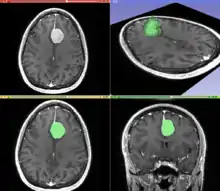

Segmentation

Segmentation is the process of partitioning an image into different meaningful segments. In medical imaging, these segments often correspond to different tissue classes, organs, pathologies, or other biologically relevant structures.[2] Medical image segmentation is made difficult by low contrast, noise, and other imaging ambiguities. Although there are many computer vision techniques for image segmentation, some have been adapted specifically for medical image computing. Below is a sampling of techniques within this field; the implementation relies on the expertise that clinicians can provide.

- Convolutional neural networks (CNN's): The computer-assisted fully automated segmentation performance has been improved due to the advancement of machine learning models. CNN based models such as SegNet,[14] UNet,[15] ResNet,[16] AATSN,[17] Transformers[18] and GANs[19] have fastened the segmentation process. In the future, such models may replace manual segmentation due to their superior performance and speed.

The figure "Visualization of Medical Imaging" illustrates several types of visualization: 1. the display of cross-sections as gray scale images; 2. reformatted views of gray scale images (the sagittal view in this example has a different orientation than the original direction of the image acquisition; and 3. A 3D volume rendering of the same data. The nodular lesion is clearly visible in the different presentations and has been annotated with a white line.